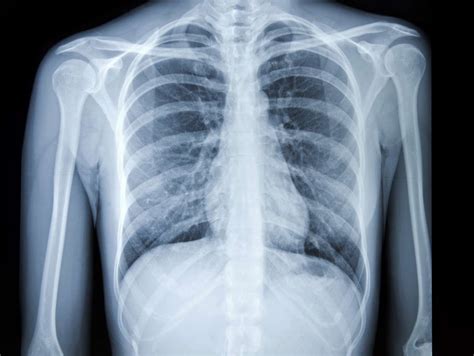

chest x-ray image

4. Imaging Tests:

• Imaging tests, such as X-rays, CT scans, and MRIs, are often included in a full body checkup to visualize internal organs and structures.

• These tests help detect abnormalities in the lungs, heart, abdomen, and other parts of the body.

• Chest X-ray: This imaging test provides a detailed view of the chest, including the lungs, heart, and major blood vessels, aiding in the diagnosis of respiratory and cardiovascular conditions.